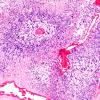

NEOPLASMS (GLIAL)

Glioblastoma, adenoid pattern (9)